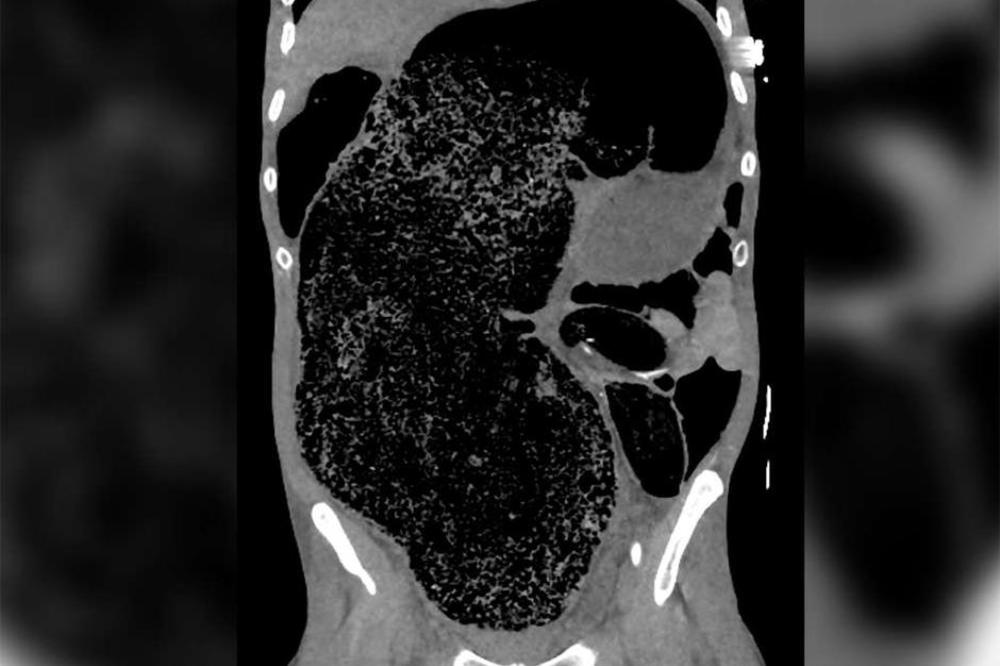

Rektalnim je pregledom utvrđeno kako ima formiranu čvrstu stolicu, a pregled trbuha ukazao je na masovno 'zbijanje fekalija', po život potencijalno opasan sindrom povećanog pritiska u abdomenu.

Lekari su obavili i skeniranje, nakon čega su uvideli da je stolica toliko rastegnula njegovo debelo crevo da je ono izvršilo pritisak na ilijačnu (bočnu) arteriju.

Taj pritisak uzrokovao je bol u nozi, kao i paralizu. Zbog ozbiljnosti njegovog slučaja (pokazivao je i znakove oštećenja bubrega i metaboličku acidozu - gde bubrezi prestaju uklanjati kiselinu iz tela), hitno je odveden na operaciju kako bi se uklonio zaostatak fekalne materije i oslobodio pritisak u trbuhu.

- Izvedeno je značajno uklanjanje fekalija u volumenu od oko 2 litre - napisao je tim u svom izveštaju.